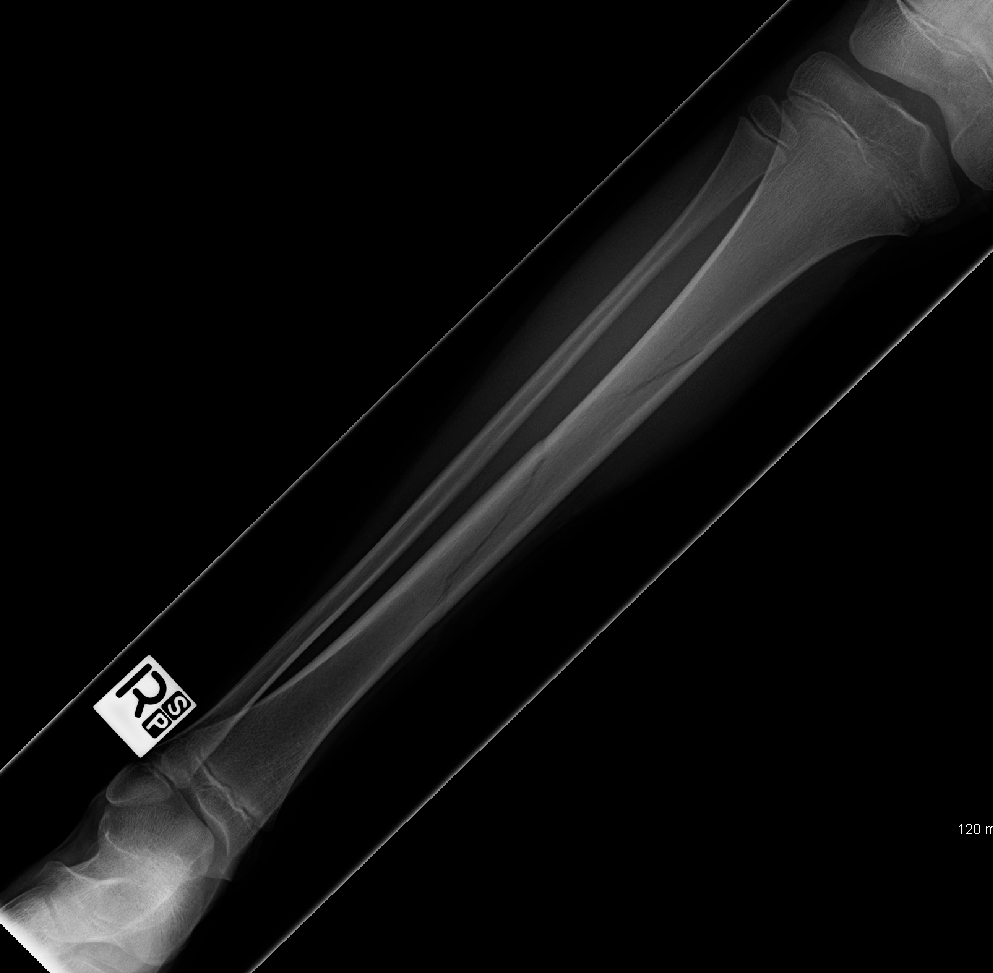

[Figure, Tibial Fracture Spiral fracture of the distal tibia

Right distal third spiral tibia fracture (a) with normal appearing Spiral Fracture Of The Tibia Spiral fractures often occur when the body is in motion while one extremity is planted. Prompt treatment is important for proper healing. The injury can also involve the long bones of the arms, including the humerus,. Spiral fracture often caused by a twisting force, this break causes a spiraling line to appear on the bone and may become unstable over. Spiral Fracture Of The Tibia.